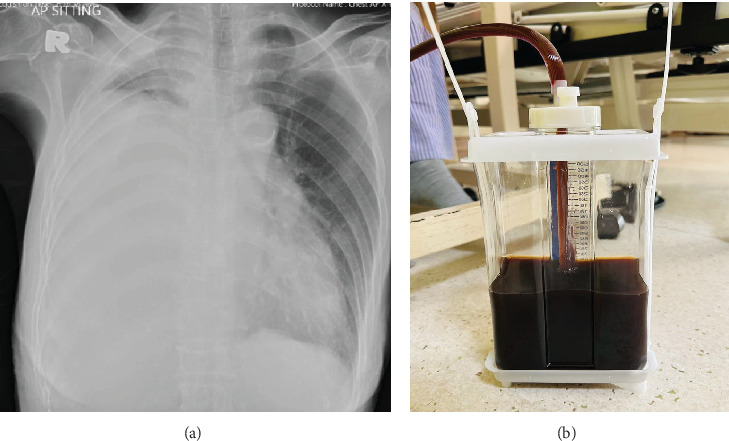

Brown-colored pleural effusion is rare and may result from high bilirubin levels such as bilothorax (often described as a pleural fluid-to-serum bilirubin ratio of > 1.0). We describe four patients with malignant pleural effusion that appeared macroscopically brown with a pleural fluid-to-serum bilirubin ratio between 3.7 and 16.2. All had metastatic adenocarcinomas; three were from lung and one from gastric origin. None demonstrated clear pleurobiliary fistulas on investigations. Postulates for the development of brown effusion include heme oxygenase 1 overexpression in malignant cells situated in the pleura, intrapleural hemolysis, passive movement of bile through microscopic diaphragmatic pores, and drainage of biliary fluid into the pleural lymphatics.